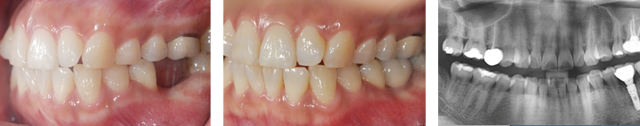

왼쪽 어금니 상실로 내원한 환자분. 어금니 임플란트의 경우 씹는 기능이 중요하기 때문에 저작능력 회복이 가장 중요합니다. 임플란트를 식립하고 강한 자극과 힘에 견딜 수 있도록 튼튼한 지르코니아 보철물로 수복하였습니다.

지르코니아는 인공 다이아몬드 재질로 강도가 우수합니다. 강한 교합력에 저항성이 강한 동시에 도자기의 심미적 장점을 함께 가져 어금니에 적합한 보철물 입니다.